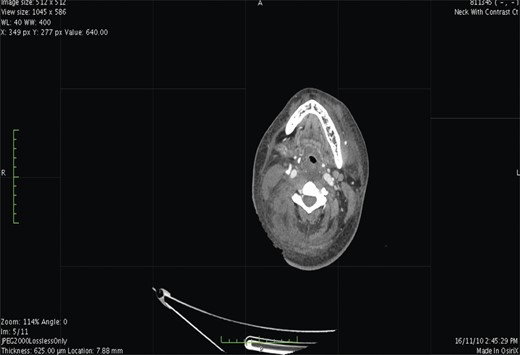

Contrast-enhanced computed tomography (CT) scan showed extensive cellulitis and thrombosis of the internal jugular vein and marked necrosis of the underlying muscles (Figs 1 and 2). The basic investigations revealed a haemoglobin level of 7.5 g/dl, a random plasma glucose level of 227 mg/dl and the fasting glucose level was 240 mg/dl.

Contrast-enhanced CT. At the level of base of skull shows airway luminal narrowing.